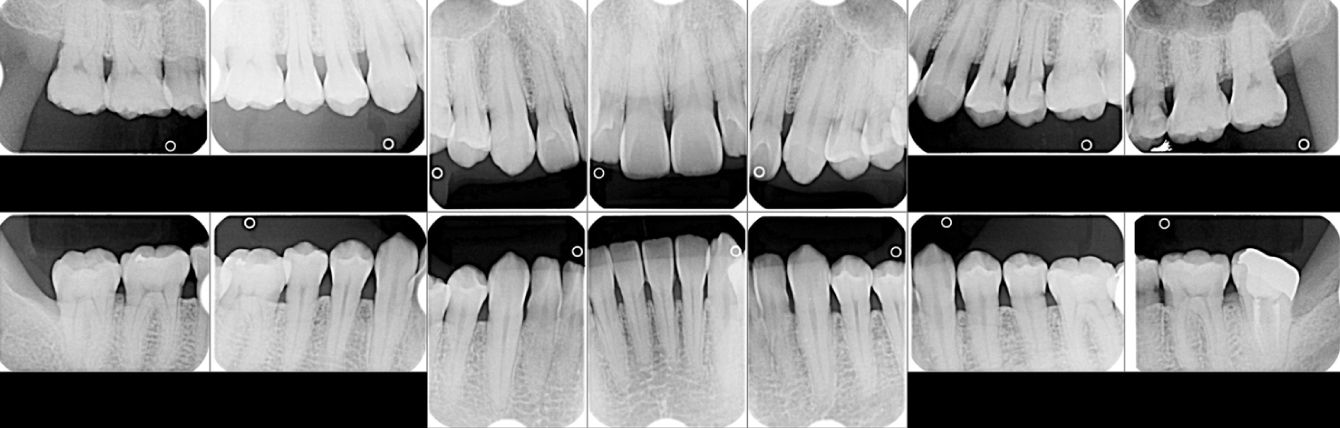

エックス線検査

まずはしっかりした診査・診断で歯周病の進行の程度について検査・資料収集を行います。

歯周病が進行するとポケットが深くなります。4mm以上になると歯周病の可能性があります。

①再評価(初期治療後の変化をチェックします)

④再評価(治療後の変化をチェックします)→②へ